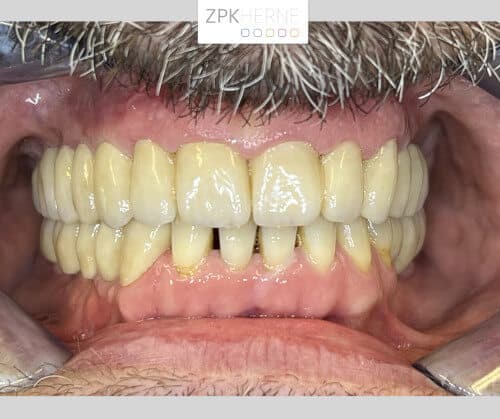

Nach 10 Jahren ohne zahnärztliche Behandlung verhelfen wir unserem Patienten zu einem neuen Lächeln

Über ein Jahrzehnt lang hat die Furcht vor dem Behandlungsstuhl unseren Patienten von dem dringend notwendigen Zahnarztbesuch abgehalten. Dabei leidet er fast schon ebenso lange unter einem nicht voll funktionsfähigen Gebiss: Seit mehreren Jahren fehlen ihm im Unter- sowie im Oberkiefer jeweils ab dem Eckzahn einige Zähne. Außerdem ist die Bisshöhe abgesackt, das heißt seit Jahrzehnten knirscht sich der Patient die Zahnsubstanz herunter. Das führt unter anderem dazu, dass er nicht mehr vernünftig essen kann. Hierfür wünscht er sich eine neue festsitzende Versorgung mittels Implantate.